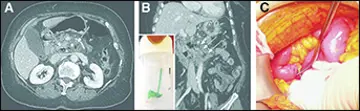

پاراگونیـمیاز

یک مرد ۱۸‌ساله با سابقه‌ی یک ساله‌ی هموپتیزی پراکنده (episodic) مراجعه کرد.